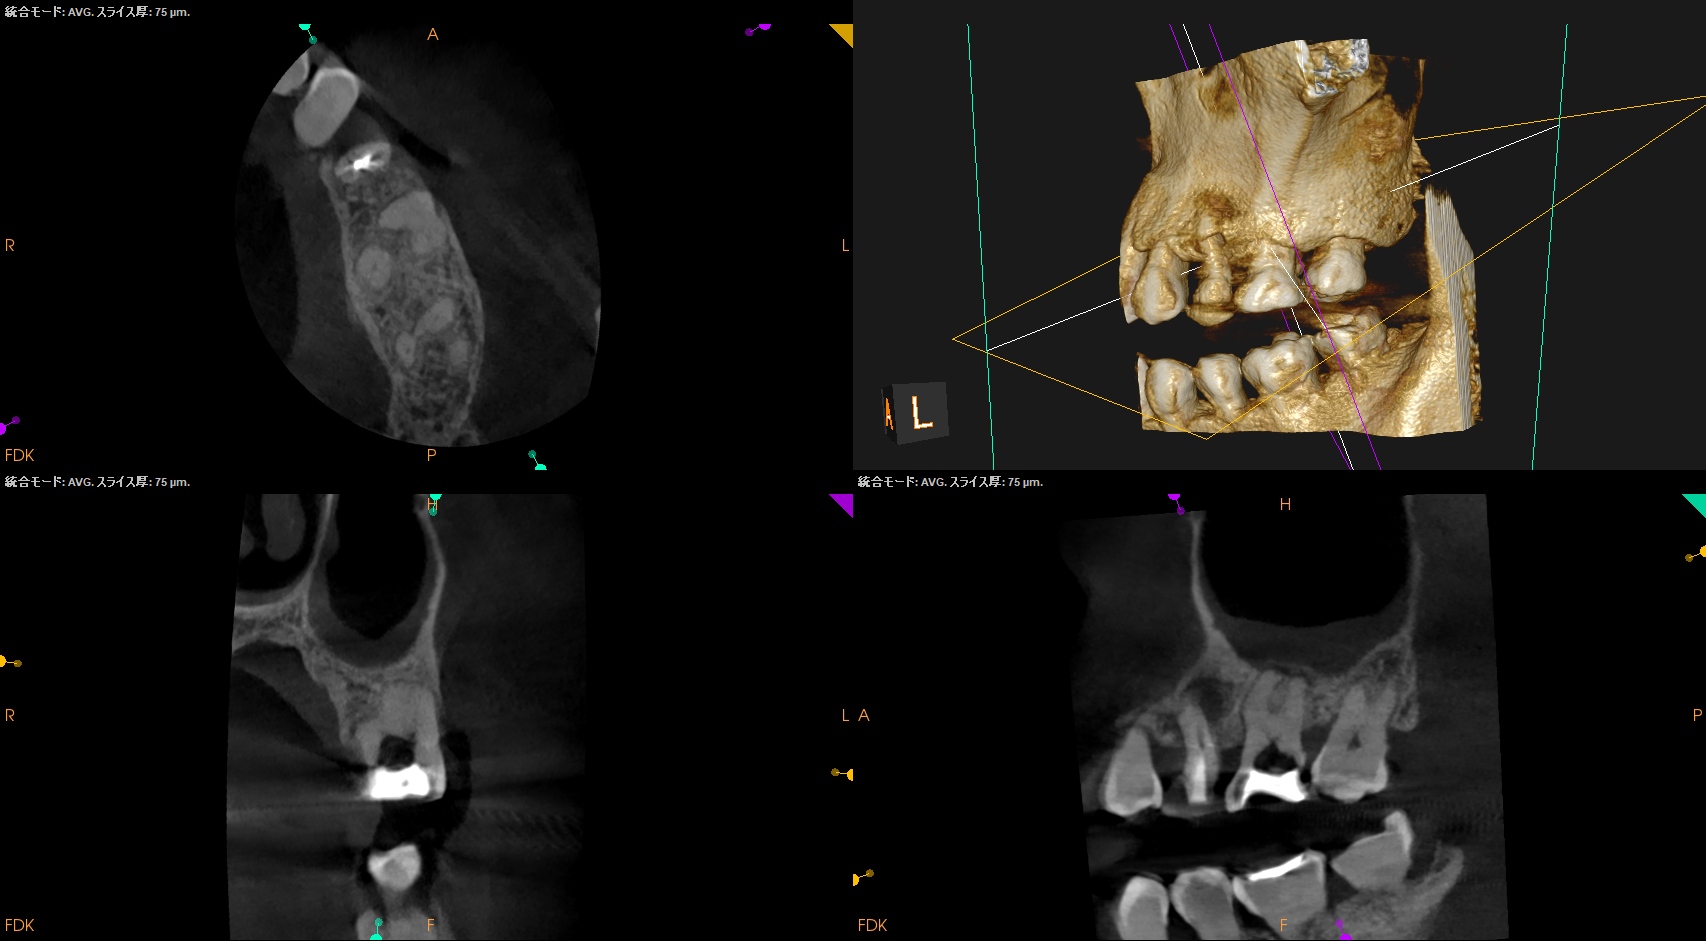

CBCTも撮影した。

これはマストの医療行為である、と私からは告げておこう。

ヨシダ社のパノラマと前述のパノラマを比較してほしい。

話にならないくらい、どちらが優れた画質であるか?ということを。

さておき、#13にも病変があるのがわかるので#13も分析した。

まだ開業していない, CBCT導入していないという未来のあるあなた。

その際には、

CareStream社のCBCTを導入することを強く勧めます。(日本では、ヨシダ社から購入できます)